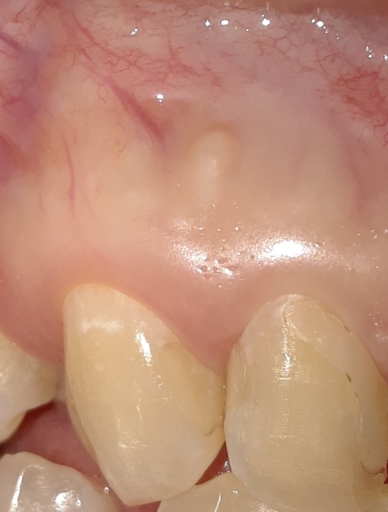

I have a question I hope you can help me with. I recently went to see my dentist because I had pain on the the left side of my mouth. It was pretty much my whole left side, top and bottom. It was very similar pain I had the year before on the right side, in which it was determined I had an infection and I needed to pull my bottom right wisdom tooth. That has since been fine. With my recent visit to my dentist with the left side she determined that I had an infection, but this time instead of pulling my one of my wisdom teeth on the left, she told me I needed a root canal on my #19 molar. I think she determined this because That tooth hurt worse than the rest and I could not eat any food with it. I ended up getting an antibiotic and within hours the pain was way less. By the next day my teeth feel perfectly normal, no pain, no sensitivity, and I can eat on that side just fine. My main concern I guess is if I really need this root canal because I do not have insurance and the procedure plus the crown afterward is very expensive. Is it possible it was just my wisdom tooth pushing on my teeth? Is it possible it was just an infection and the tooth is still alive? What would happen if I put off the root canal procedure and it turned out I really needed it, at some point would it be too late in the future to do it?